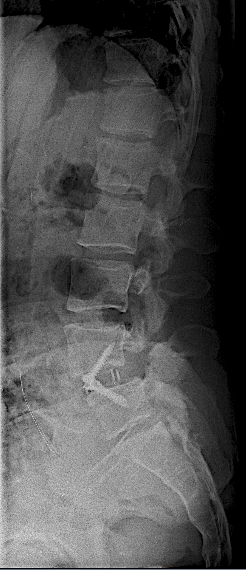

Tras retirada de faja, la paciente seguía presentando lumbalgia mecánica. Obsérvese la lisie de la pars.

En la RM lumbar de control se apreciaba edema en L5-L6 que se interpretó como secundario a sobrecarga mecánica a dicho nivel. Se decidió una fijación percutánea (MIS) L5-L6.

Tras la fijación percutánea, la paciente seguía presentando lumbalgia mecánica (de menor intensidad). Tras agotar opciones de tratamiento conservador, atribuimos como causa la discopatía incipiente L4-L5 (que había progresado).